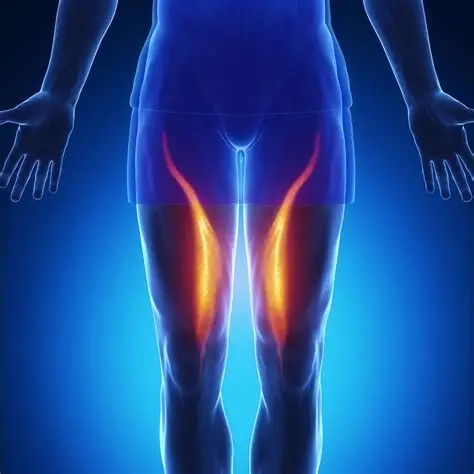

Hamstring Strain